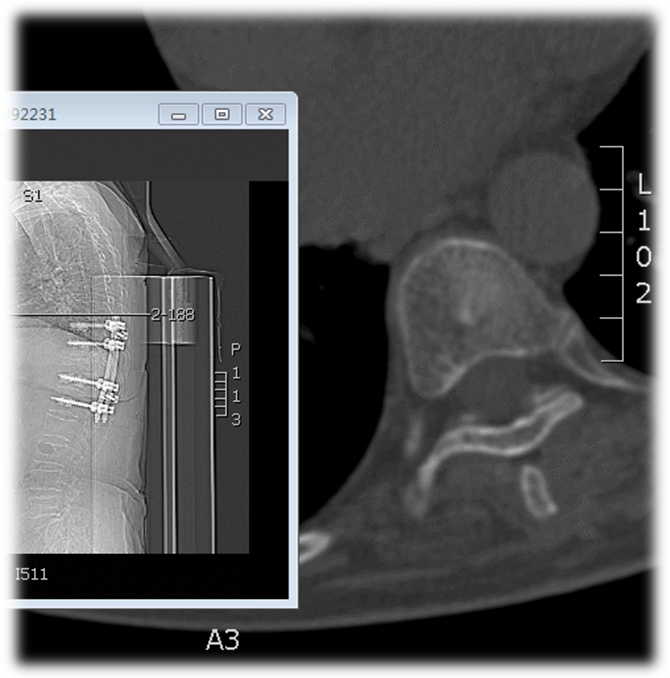

术前CT

术中透视

术后X线

术后CT